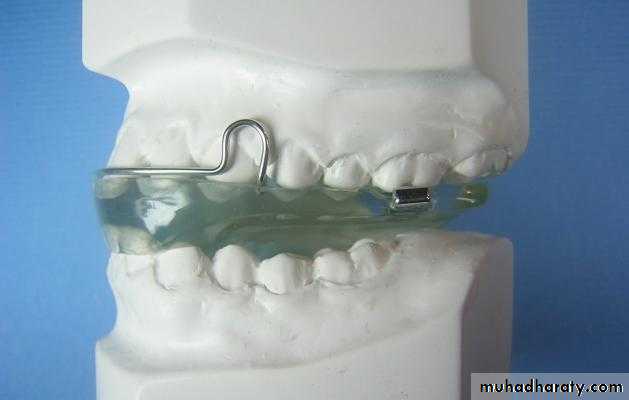

LIP BUMPER

• “combined removal-fixed appliance”. • Used in both maxilla & mandible to shield the lips away from the teeth.• Uses:

-in lip sucking patients.

-hyperactive mentalis activity.

-to augment anchorage

-distalization of first molars